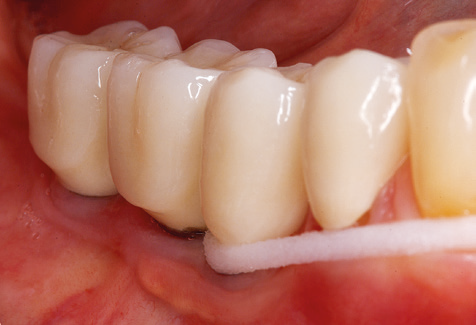

Für den klinischen Langzeiterfolg des parodontal kompromittierten Patienten ist die standardisierte und regelmäßige risikoadaptierte Betreuung im Rahmen der UPT der zentrale Baustein des Behandlungserfolgs. Dies gilt in besonderer Weise für Patienten, die nach erfolgreich abgeschlossener parodontaler Sanierung mit Implantaten versorgt wurden (Abb. 11a und b).